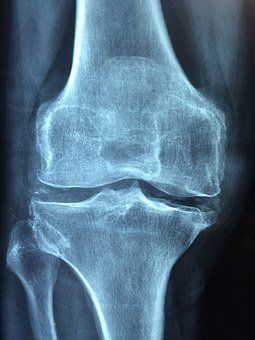

Nachdem die Akutbehandlung (auch medizinische Rehabilitation) einer Erkrankung (z. B. Operation, medikamentöse Therapie, Verheilung von Brüchen / Verletzungen) abgeschlossen ist, kann der/die Patient*in in die stationäre Rehabilitation übergeben werden. Diese dauert in der Regel 3 bis 6 Wochen und bewirkt, dass der/die Geschädigte den Alltag wieder eigenständig oder mit Unterstützung (bei Pflegegrad) bewältigen kann. Wenn eine ausreichende Mobilität und Belastbarkeit gewährleistet ist, kann eine ambulante Reha der stationären Reha vorgezogen werden. Die Entscheidung über die Durchführung wird stets von Ihrem Arzt oder Ihrer Ärztin getroffen. Nach der ambulanten oder stationären Rehabilitation ist eine Nachsorge notwendig - die Anschlussrehabilitation oder Nachsorgerehabilitation. Hierfür stehen verschiedene Nachsorgeprogramme zur Verfügung, z. B. T-RENA (Trainingstherapeutische Rehabilitationsnachsorge). In der Regel werden die Funktionseinschränkungen am Haltungs- und Bewegungsapparat in mindestens 26 Terminen (Verlängerung bei Bedarf möglich) mithilfe von Muskelaufbautraining, medizinischer Trainingstherapie und Krafttraining abgemindert.